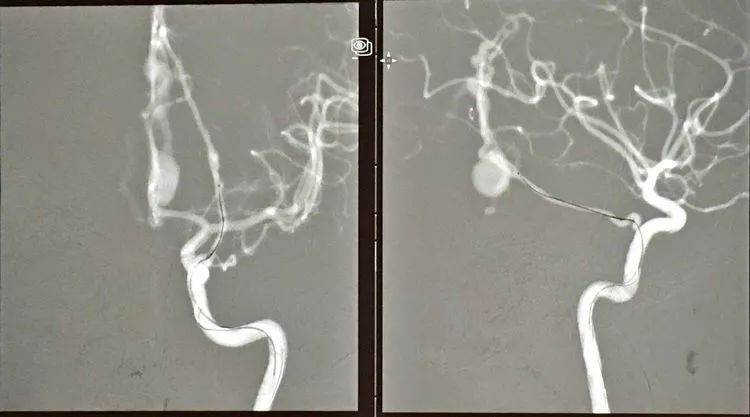

CASE 1 DAVF

-动脉入路栓塞:颈内动脉脑膜垂体干;大脑后动脉的硬膜供血分支

-可解脱的Apollo微导管(3cm,1.5cm)

-栓塞材料是PHIL,CT伪影小

-DAVF含有软膜血管的供血,有医生提出可能需先栓塞,但多数专家包括Wakhloo,Civan等认为这些供血最终还是供应到硬膜上的,也就是说软膜血管没有直接瘘到静脉,它们之间还有硬模膜上的动脉,软膜血管只是近端的供血动脉,他们认为不栓塞软膜供血动脉而通过硬模膜供血完全闭塞静脉端应该可行